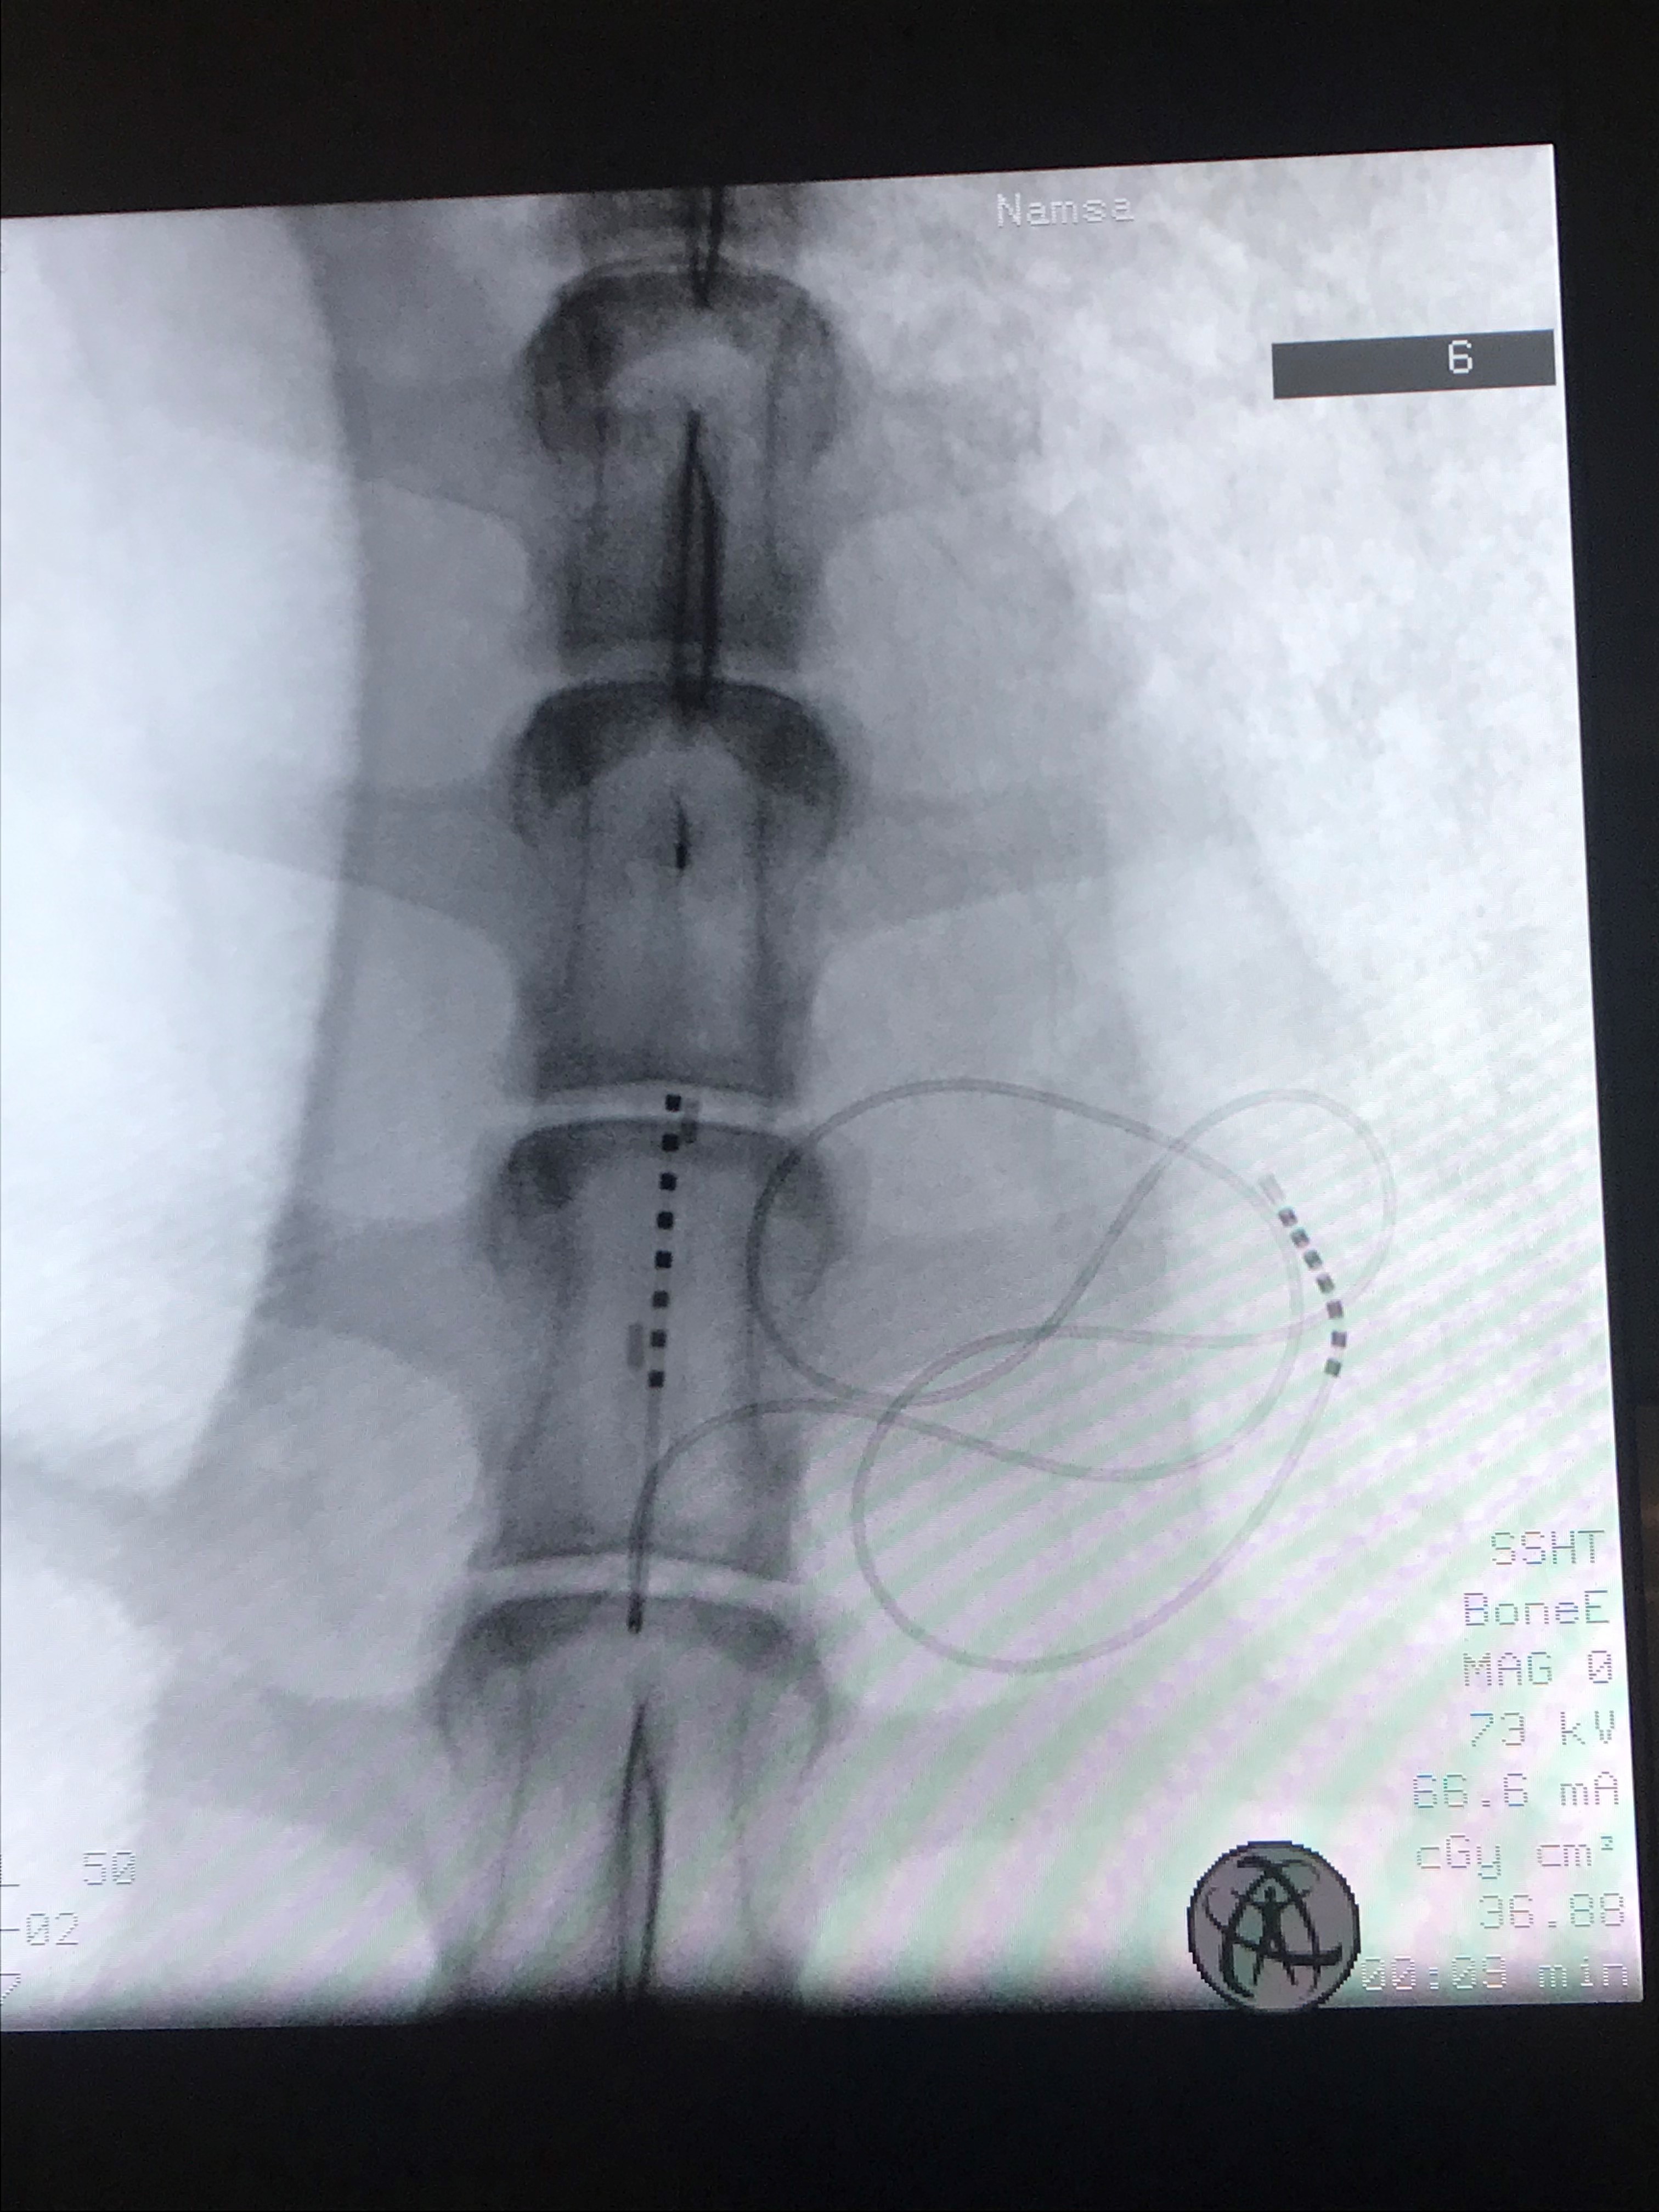

Paddle in a sheep spine, markers and rings are visible under fluoroscopy

Our prototype demonstrated for the first time, to our knowledge, its capability to insert a multicolumn paddle lead percutaneously via a mini-invasive procedure. The prototype consists of a multicolumn paddle lead folded in a catheter that can be pushed in the subdural space of the spinal cord and deployed at the therapeutical site. In the final configuration of the product the leads have been tested in its final configuration and the full mini-invasive procedure have been demonstrated. This allow for the first time, to achieve a minimally invasive implantation of this type of electrodes, which will allow to reach overall savings of up to €140,000 per patient by avoiding a complex and invasive surgery.